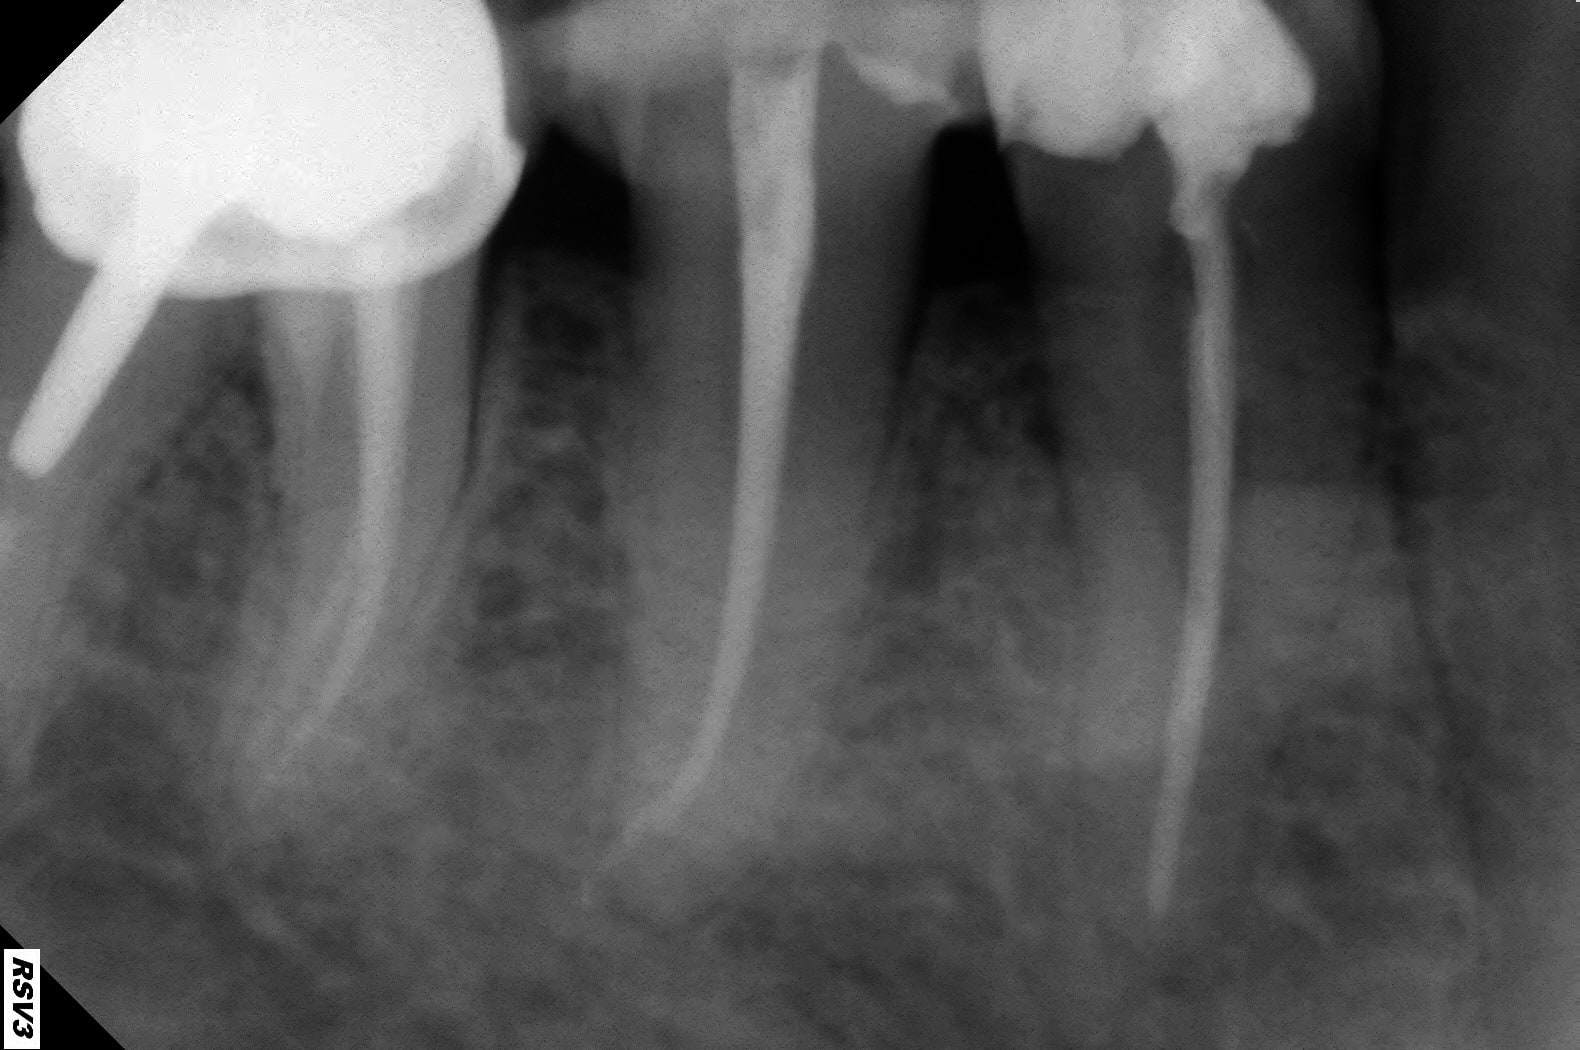

Exemple perfo magistrale en 2009, et radio 2013 et 2017 (on ne vois que la racine mésiale mais la furcation tient le coup.

46 2009 2 fujwq5 - Eugenol

46 2017 ra1wjf - Eugenol

46 2013 rwugpl - Eugenol

46 2009 cxmhe5 - Eugenol

Merci pour les photos.cela ressemble à ce qui s'est passé pour moi.j'ouvre tes la chambre avec une fraise endormi z donc je n'avais jamais eu de soucis de perfo sur une ouverture de chambre.